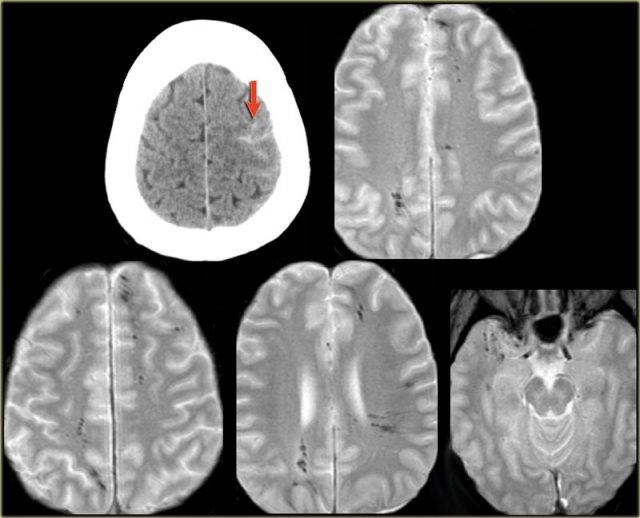

Tổn thương sợi trục lan tỏa (DAI)

Một người đi xe đạp 46 tuổi nhập viện với triệu chứng co giật sau khi bị xe ô tô đâm.

Hình ảnh CT chỉ cho thấy xuất huyết dưới nhện tối thiểu (mũi tên).

MRI được thực hiện vài tuần sau chấn thương do bệnh nhân có thay đổi nhân cách.

Chuỗi xung T2* cho thấy nhiều ổ lắng đọng hemosiderin tại vùng ranh giới giữa chất xám và chất trắng, phù hợp với tổn thương sợi trục lan tỏa (DAI).

Lưu ý vị trí của các vi xuất huyết này khác với các ổ xuất huyết CAA nằm ở ngoại vi.